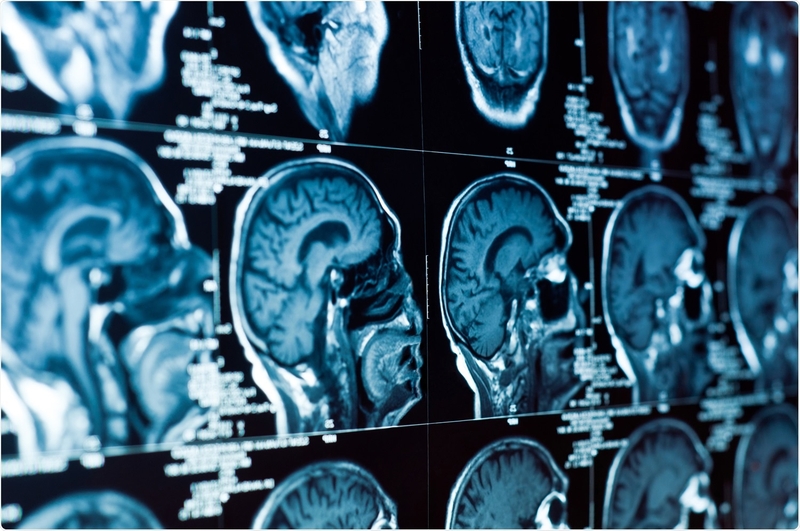

Hậu F0 nhiều người vẫn gặp phải một số khó khăn về nhận thức.

Di chứng nhận thức ở người khỏi Covid-19 vừa được phát hiện 2F0 điều trị hồi sức tích cực có nguy cơ giảm khả năng chú ý, trí nhớ và điều khiển hành vi cao.